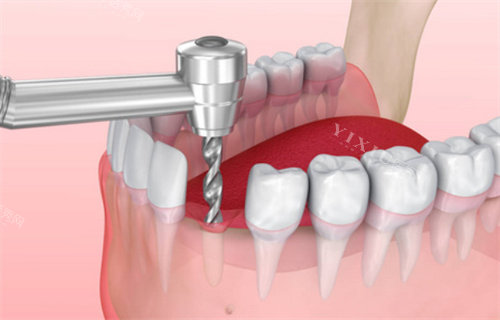

种植牙项目

百康特种植体:3000元起

奥齿泰种植体:5800元起

瑞士ITI种植体:12800元起

诺贝尔种植体:15800元起